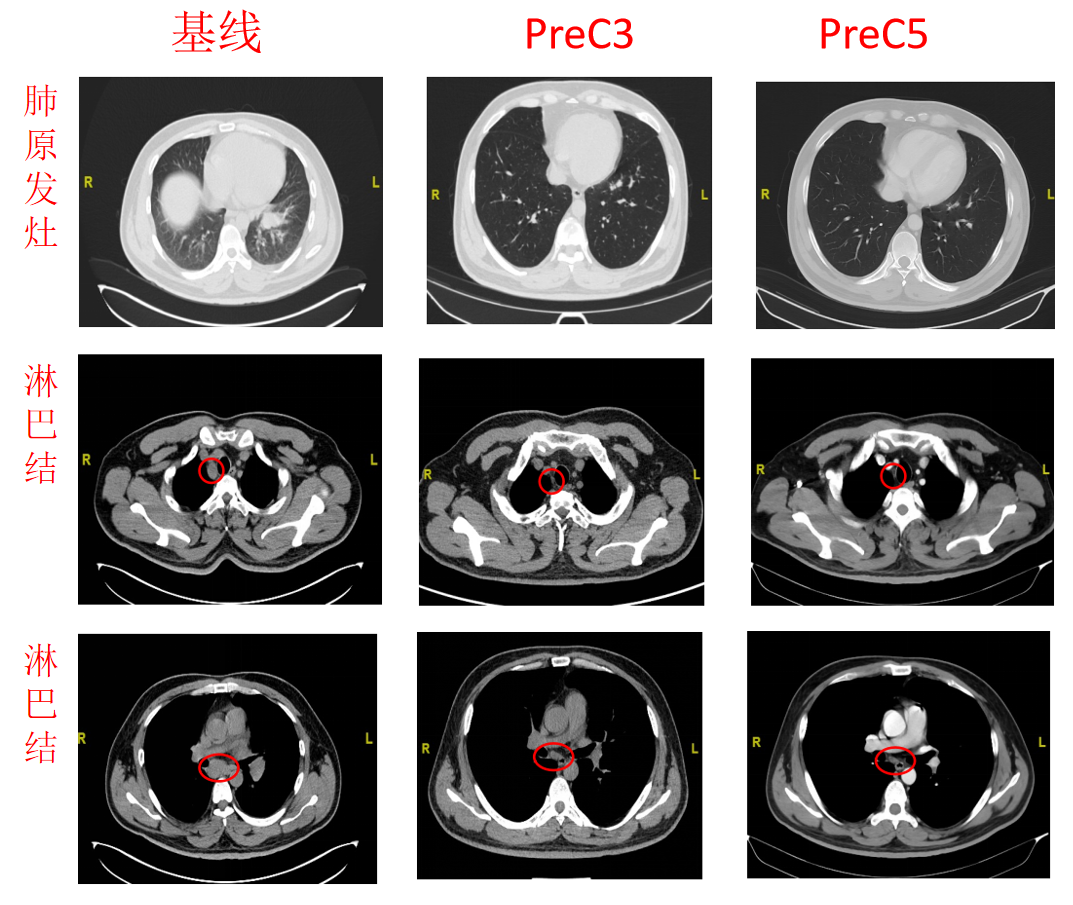

影像学检查:

PreC3:

CT(2022.7.5):左肺MT治疗后,左肺下叶近肺门软组织密实,牵拉临近胸膜。两侧胸廓对称,两肺纹理清晰,走向自然,余肺叶内未见明显异常密度阴影。纵膈稍大淋巴结。

PreC5:

CT(2022.8.22):左肺MT治疗后,左肺下叶近肺门软组织密实同前,牵拉临近胸膜。两侧胸廓对称,两肺纹理清晰,走向自然,另左肺下叶小结节,大者约4mm。纵膈未见明显淋巴结。肝内多发结节。

图5.基线、C3、C4的胸、腹CT和MR影像